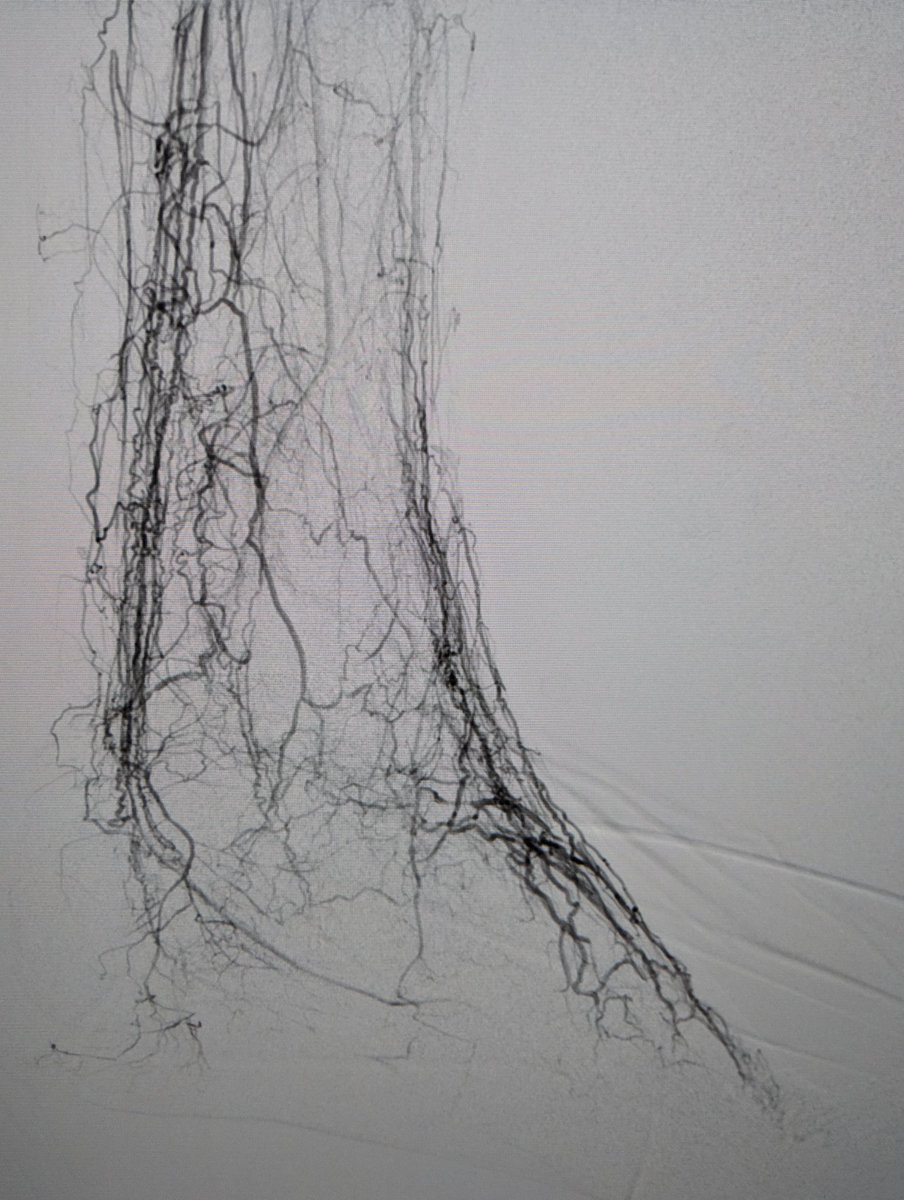

#CLIFighters #MyLegMyLife Special thanks to my colleague Benjamin Pomerantz, MD for his codification of intraoperative sweat accumulation. This is a Classic Pomerantz IV (extension to popliteal fossa)